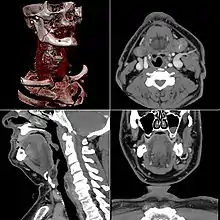

Images obtenues par tomodensitométrie.

- Technique d’imagerie électronique qui consiste à mesurer l’absorption des rayons X par le matériau analysé (tissu humain ou animal ou matière inerte) puis, par traitement informatique, à numériser et enfin reconstruire une image en deux ou trois dimensions des structures anatomiques, végétales ou minérales étudiées.